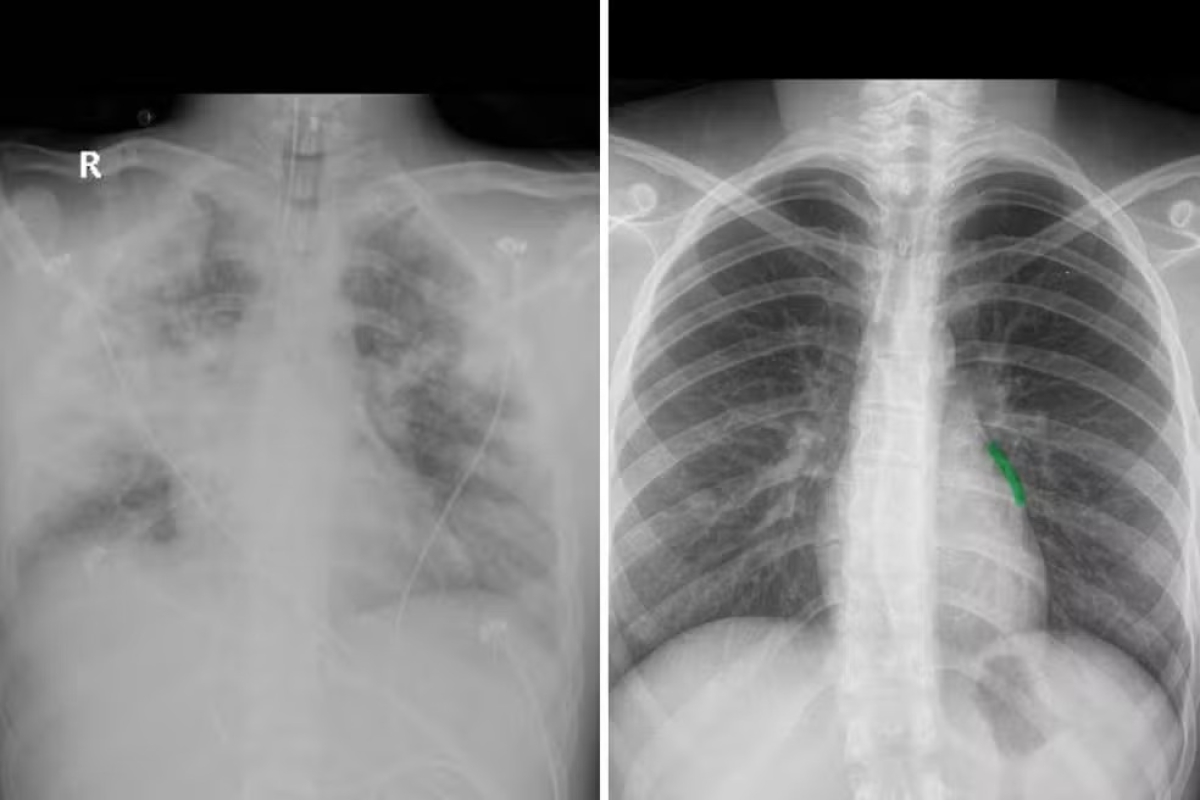

Do lado esquerdo, imagem do pulmão de Diego todo comprometido. Do lado direito, a imagem de um pulmão saudável - Foto: Divulgação